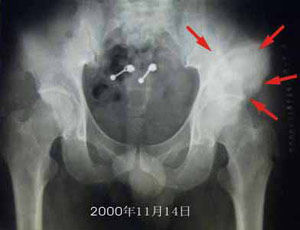

骨盆癌影像學表現骨盆環是由骶骨和兩側的髖骨組成,每側髖骨由髂骨、坐骨和恥骨構成。骨盆被肌肉所覆蓋,這些肌肉起到了限制腫瘤直接侵犯鄰近血管神經束的作用。例如,當髂骨腫瘤突破骨皮質向內或向外生長時,總是有肌肉覆蓋在腫瘤表面,外側有臀肌包裹,內側有髂肌和腰肌,這些肌肉均有明顯的筋膜覆蓋(特別是起於髂嵴的髂肌),是防止腫瘤向腹部及盆腔擴散的良好屏障。

發生於恥骨的腫瘤鄰近經過恥骨支前面的股神經血管束,但這些血管神經束有較厚的筋膜,使之不易被腫瘤直接侵犯。坐骨神經在坐骨大切跡處與骨盆最接近,當腫瘤蔓延至坐骨切跡時可以緊鄰坐骨神經。發生於恥骨聯合部位的骨盆腫瘤相對較少,對此部位的腫瘤進行手術時應注意保護膀胱和尿道。

骨盆癌的診斷主要依據影像學檢查及組織病理檢查表現。

MRI

非常有助於判斷腫瘤的範圍和對輔助治療的反應。由於MRI可以顯示腫瘤三維六個方向上的範圍,因此可以用於計畫各個方向上的切除邊界,即MRI可以顯示腫瘤在遠、近、內、外、前、後各個方向上的範圍,並以此為依據計畫各方向上相應的切除邊界,發現最困難的切除部位,完善術前準備。